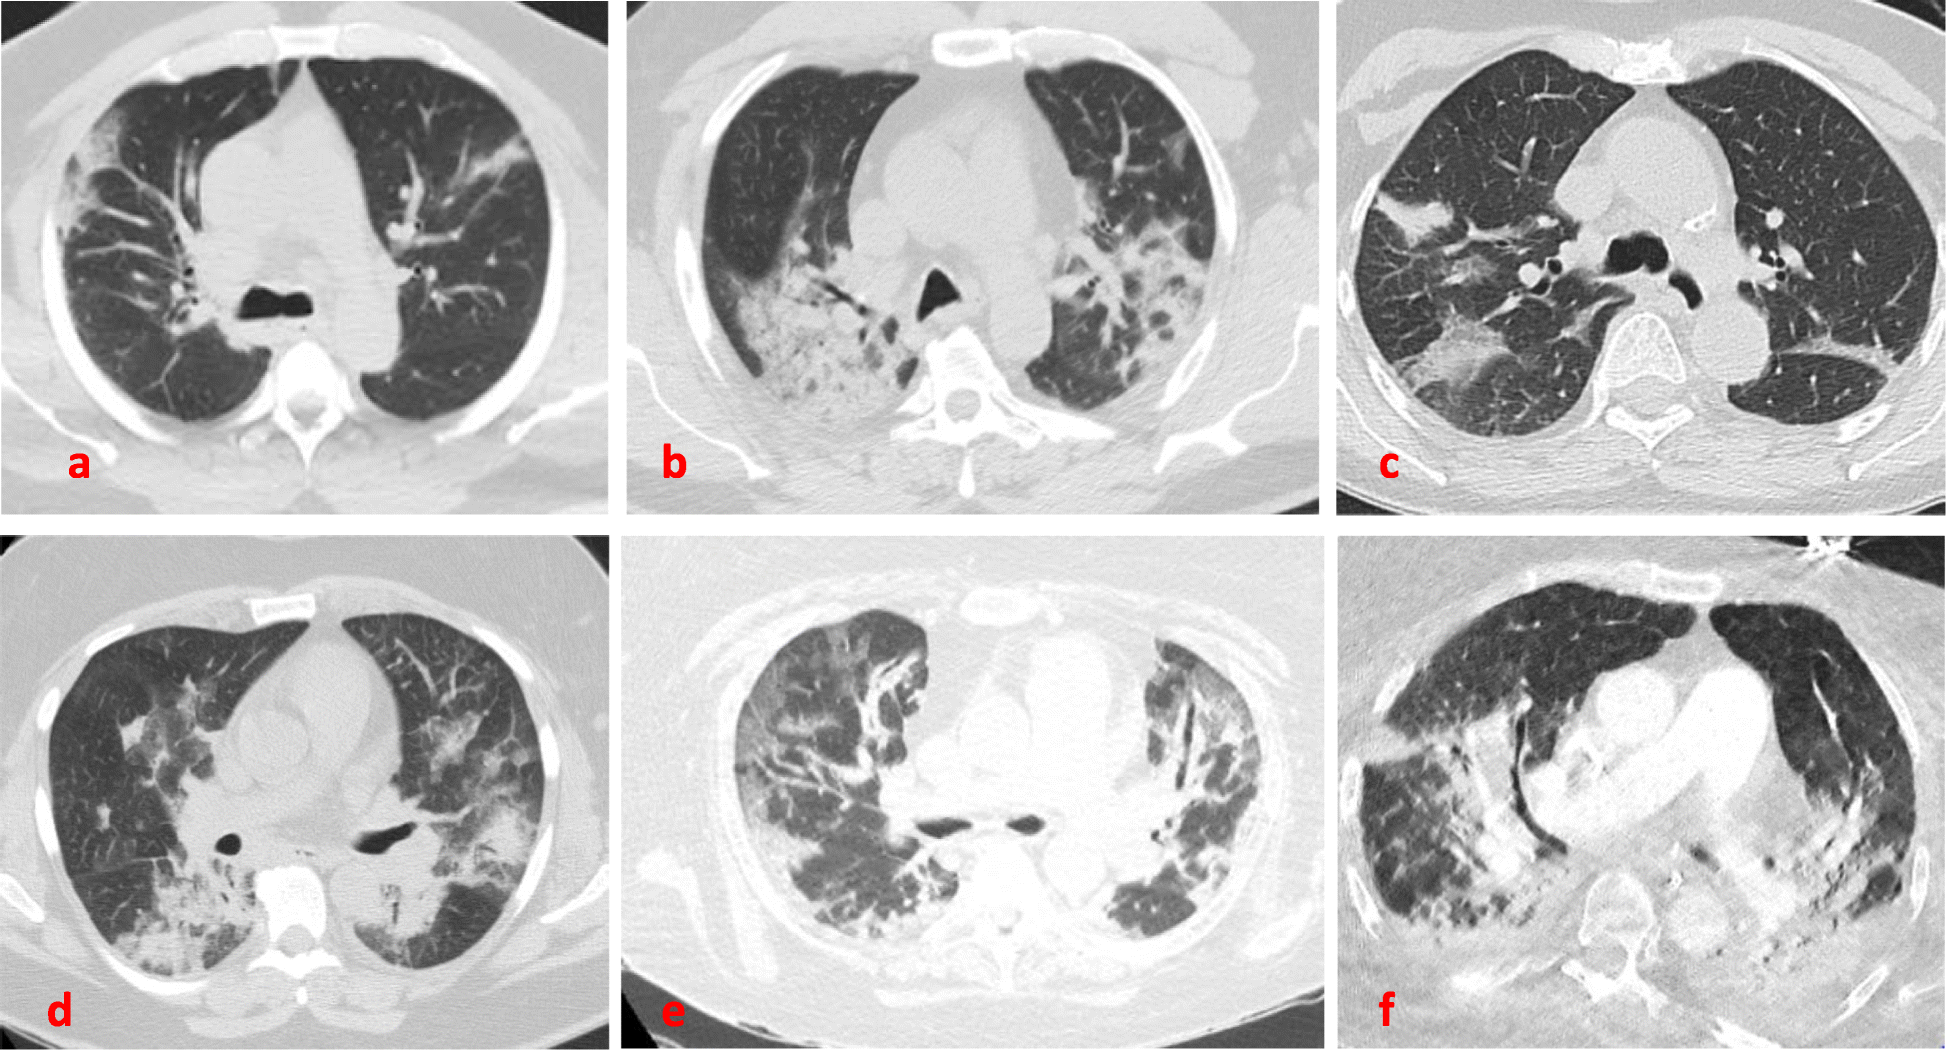

Baseline CT scan of the chest. Areas of GGOs, consolidations and crazy paving seen commonly bilaterally, more predominant in the posterior and peripheral lung regions. From top left: a Case-1. b Case −2. c Case −3. d Case-4. e Case-5. f Case 6